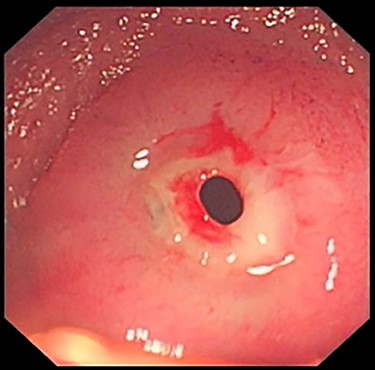

Initial investigations included magnetic resonance enterography that was normal and a capsule endoscopy that showed rare erosions, aphthoid ulcers and two ulcerated stenosis (Fig. 1).